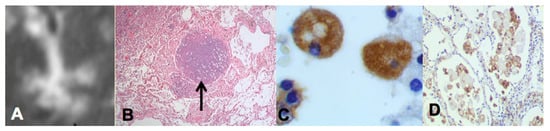

Two recent findings contributed to the formation of a new paradigm. First, bronchial obstruction has been found in 100% of cases of pulmonary TB by many pathologists and is the basis of the tree-in-bud sign that is characteristic of advancing TB on CT scans [3,15,19,25] Figure 2A,B. In addition, bronchial obstruction produced by cancer or other disease causes an endogenous lipid pneumonia that resembles developing post-primary TB, including the propensity to undergo caseous like necrosis and cavitation [26,27]. Finally, relief of bronchial obstruction has produced rapid regression of pulmonary TB [15,17,28].

The second finding that contributed to the new paradigm is that secreted, but not somatic, mycobacterial antigens accumulate asymptomatically for months in foamy alveolar macrophages in developing post-primary TB [22], Figure 2C,D. Mustafa et al. reported and we have confirmed that these are secreted, not somatic, antigens of MTB [29]. Such antigens remain intracellular with little or no inflammatory reaction until onset of massive inflammation and caseous necrosis. Scientists have long puzzled over how very few bacilli could produce such sudden massive necrosis in the lung. The finding of secreted mycobacterial antigens slowly and quietly accumulating in foamy alveolar macrophages in the preclinical stage of bronchogenic TB provides a plausible answer. Foamy alveolar macrophages, long thought to be part of non-specific inflammation, are now recognized as major players in the pathogenesis of post-primary TB.

Figure 2. Bronchial obstruction and intracellular accumulation of MTB antigens in developing post-primary TB. The tree-in-bud sign on high resolution CT scan (A) is characteristic of developing post-primary TB. It is formed by obstructed bronchioles (tree) and alveoli filled with foamy macrophages (buds). Bronchial obstruction (arrow in B) is found in 100% of cases of TB (H&E, 40 magnification). Immunohistochemistry (IHC) stain with rabbit polyclonal antibody against whole killed MTB (C,D) shows MTB antigens to be intracellular in alveolar macrophages in viable lung tissue. MTB are seldom found in such lesions by either IHC or AFB staining suggesting that very few MTB secrete antigens that are stored for a prolonged period in these cells prior to induction of caseous pneumonia. (C 700×, D 100× magnification).